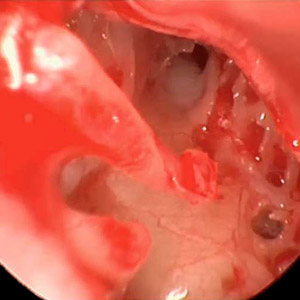

Endoskopischer Blick in die Ohrtrompete